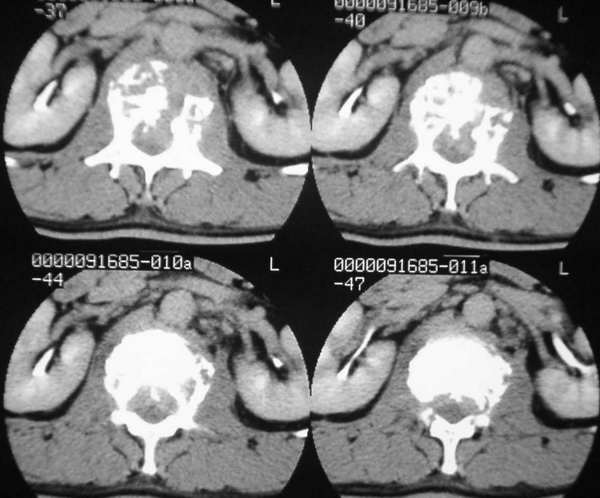

男,42岁。半年前体检发现右侧肺门肿大,mri示右侧肺门淋巴结肿大。腰背部疼痛伴右腿麻木1月入院。腹部b超示肝、胆、胰腺、脾、肾、前列腺及膀胱未见异常。afp、cea、ca199均正常。

增强图像显示不清,好像有肺门及纵隔与腋下淋巴结肿大,右侧胸腔积液,腰1椎体骨质破坏,椎旁软组织肿块形成,其后硬脊膜囊明显受压。考虑淋巴瘤可能。其他待排。

腰椎骨质破坏,但未侵及椎间盘,椎前软组织肿胀,考虑腰椎转移瘤可能

腰椎骨质破坏,但未侵及椎间盘考虑腰椎转移瘤可能

请问腰椎ct有没有平扫的,有没有骨窗位的,怎么在mri上有条片状信号缺失区,所以,结合平片我认为椎体血管瘤也无法排除????